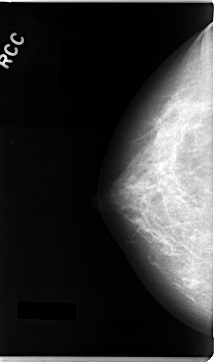

C_0026_1.RIGHT_CC

RIGHT_CC LINES 4720 PIXELS_PER_LINE 2784 BITS_PER_PIXEL 12 RESOLUTION 50 NON_OVERLAY